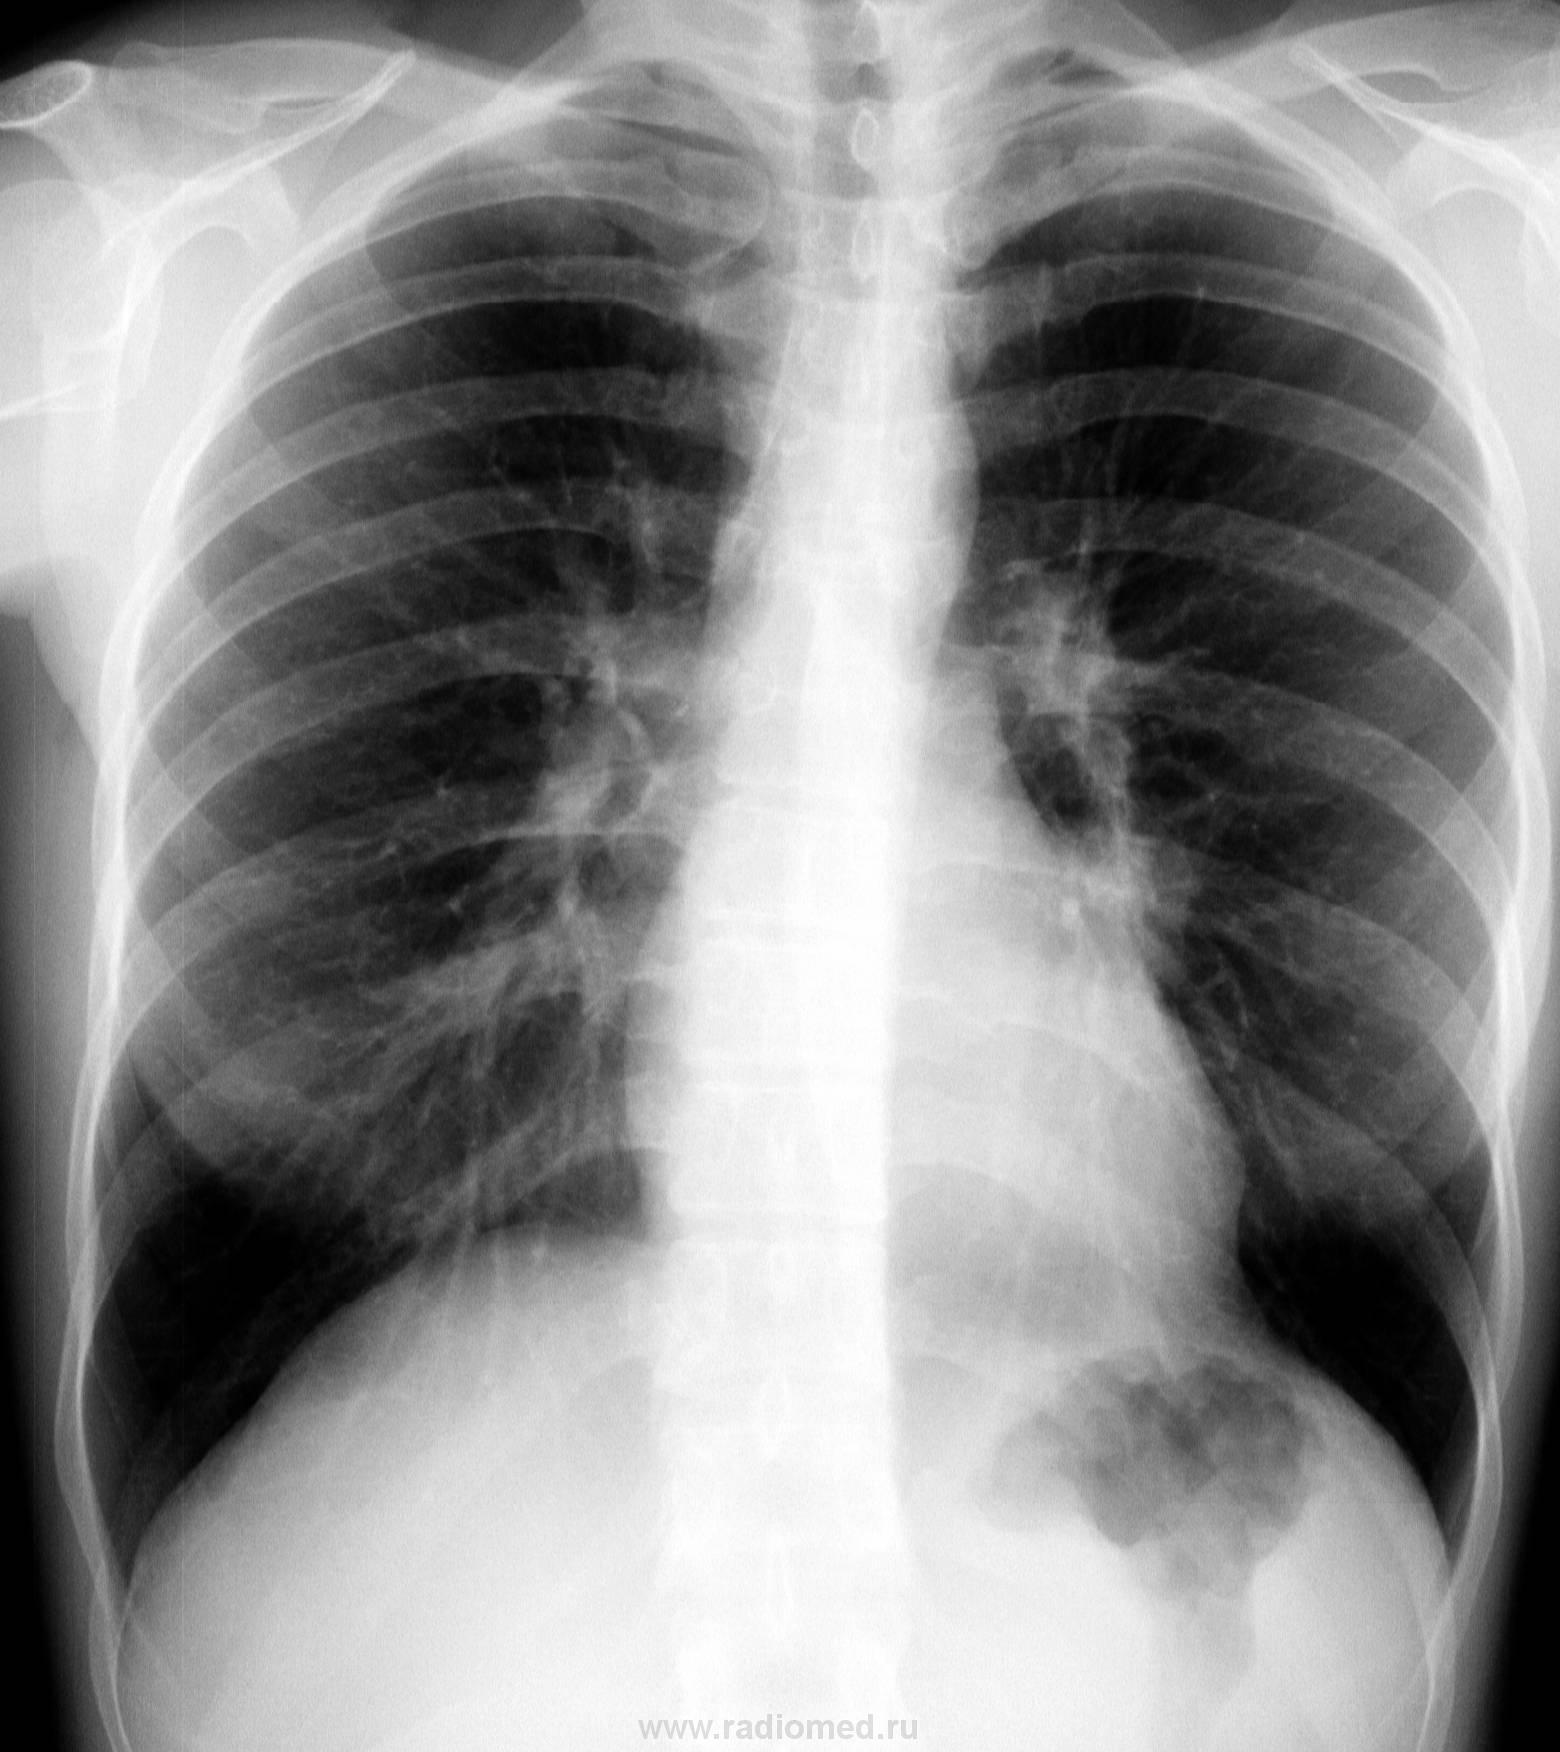

Молодая барышня 28 лет. На момент проведения ц ФГ жалоб нет. Представлена для контроль аналоговая рентгенограмма двухнедельной давности. Динамика отсутствует (посему не выставляю)

В тот же день проведена КТ (о результате информирован лечащим врачом). Ваше мнение?

Шаровидная тень: в S4 в/доли слева (1 случай) и S10 н/доли справа (2 случай)

Татьяна Валентиновна, асолютно согласен. что основной рентгенологический признак - шаровидные тенеобразования, но...достаточно ли они "шаровидны" и достаточно ли однородны....+молодой, в общем то возраст, + отсутствие существенных жалоб. Конечно, смущает тот факт, что это не первые их ФГ (но у меня то они впервыеwink). Опять же - в С10 (скрывается за тенью печени), в С4 слева (не факт, что раньше было перекрыто левым краем сердца) и, как следствие - не были обнаружены.

Внутрилегочная секвестрация или артериовенозная мальформация.

..... артериовенозная мальформация.

Она самая))). Да, оба случая подтверждены на КТ.